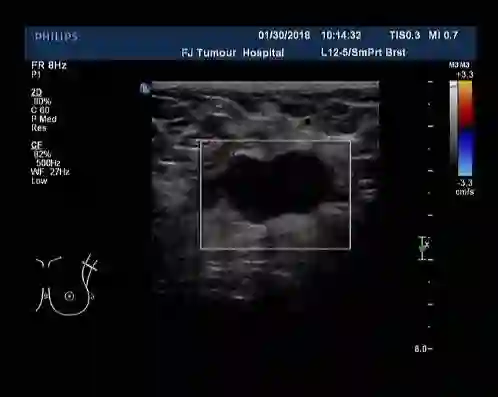

2018-05-25、2018-06-14改为nab-PHL方案(白蛋白结合型紫杉醇400mg+曲妥珠单抗408mg+拉帕替尼1000mg )化疗2周期。

▎疗效评估:B超(2018-07):左乳2-3点处探及一低回声区,大小约2.2cm×1.4cm,边缘不规则,可见成角、毛刺,内部回声不均;左腋中、下组探及数个低回声,大者约1.6cm×0.7cm(腋中组)、0.9cm×0.5cm(腋下组),边界尚清,类圆形,皮髓质分界不清,皮质不规则增厚,淋巴结门消失,右乳及右腋窝未见异常。